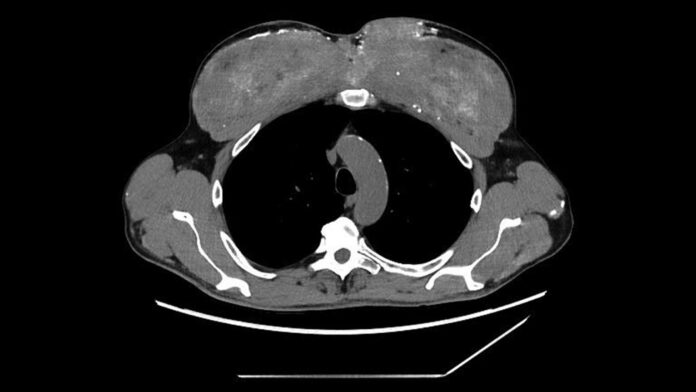

Спочатку пацієнт звернувся за допомогою до блювоти та незрозумілої втрати ваги. Аналізи крові показали ниркову недостатність і критично підвищений рівень кальцію. Візуалізація показала поширені відкладення кальцію в основних органах, включаючи нирки, підшлункову залозу та шлунок, а також кальцифіковані аномалії в грудних м’язах. Незважаючи на початкове лікування для зниження рівня кальцію, вони знову зросли, що призвело до госпіталізації у нефрологічне відділення.

Біопсія м’язів підтвердила наявність маслянистої речовини, що відповідає синтолу, агенту, що збільшує м’язову масу, що містить переважно тригліцериди середнього ланцюга. Тіло пацієнта відреагувало на неперетравлену олію, спричинивши хронічне запалення, рубці та, зрештою, великі відкладення кальцію в м’язовій тканині. З часом цей кальцій просочується в кров, викликаючи важку гіперкальціємію.